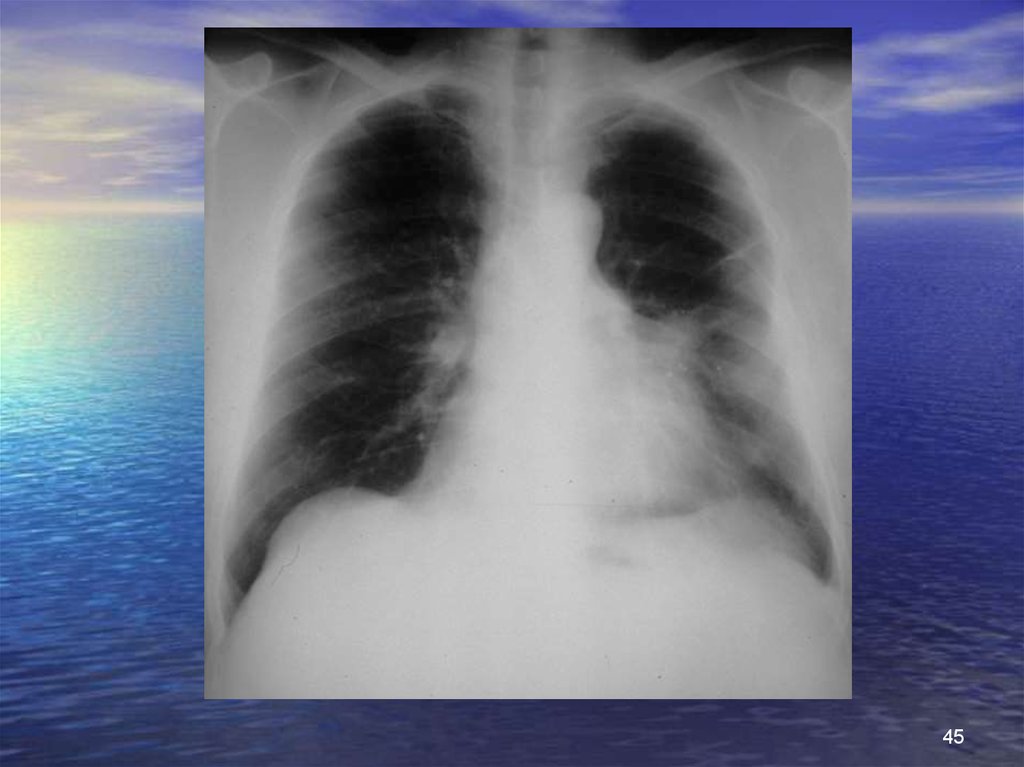

45.

45